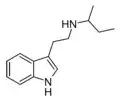

| NSBT | artificial | H | H | CH(CH3)CH2CH3 | N-sec-butyltryptamine | |